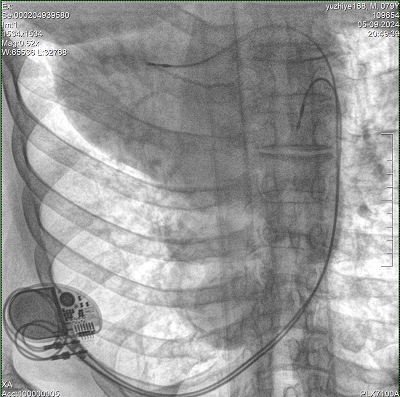

具備血管造影及數(shù)字減影(DSA)、路徑圖(Road-map)、透視、攝影等功能。 廣泛適用于介入科、血管外科、腫瘤科、消化內(nèi)科及骨科等多個(gè)臨床科室,典型應(yīng)用包括:TACE(肝腫瘤栓塞與化療灌注術(shù))、心臟起搏器置入術(shù)、四肢動(dòng)脈造影術(shù)、下肢靜脈濾器置入術(shù)、ERCP(經(jīng)內(nèi)鏡逆行胰膽管造影術(shù))等。

設(shè)備搭載自主研發(fā)的大功率高壓發(fā)生器、高熱容球管與大尺寸平板探測(cè)器,配合先進(jìn)圖像處理算法及高效冷卻循環(huán)系統(tǒng),能夠在長(zhǎng)時(shí)間手術(shù)過(guò)程中持續(xù)輸出高清圖像并保持幀率穩(wěn)定。